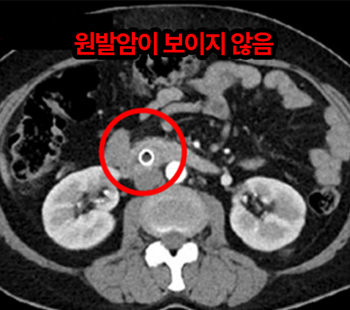

2023.2.2 腹部CT

胰腺 低分化腺癌 4期 诊断

实施抗癌治疗 & 高频热疗